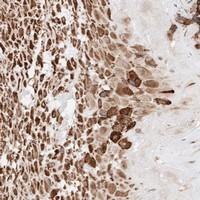

- Immunohistochemical staining of human placenta with ATP9B polyclonal antibody (Cat # PAB22275) shows strong cytoplasmic positivity in decidual cells at 1:20-1:50 dilution.

- Immunohistochemistry (Formalin/PFA-fixed paraffin-embedded sections)